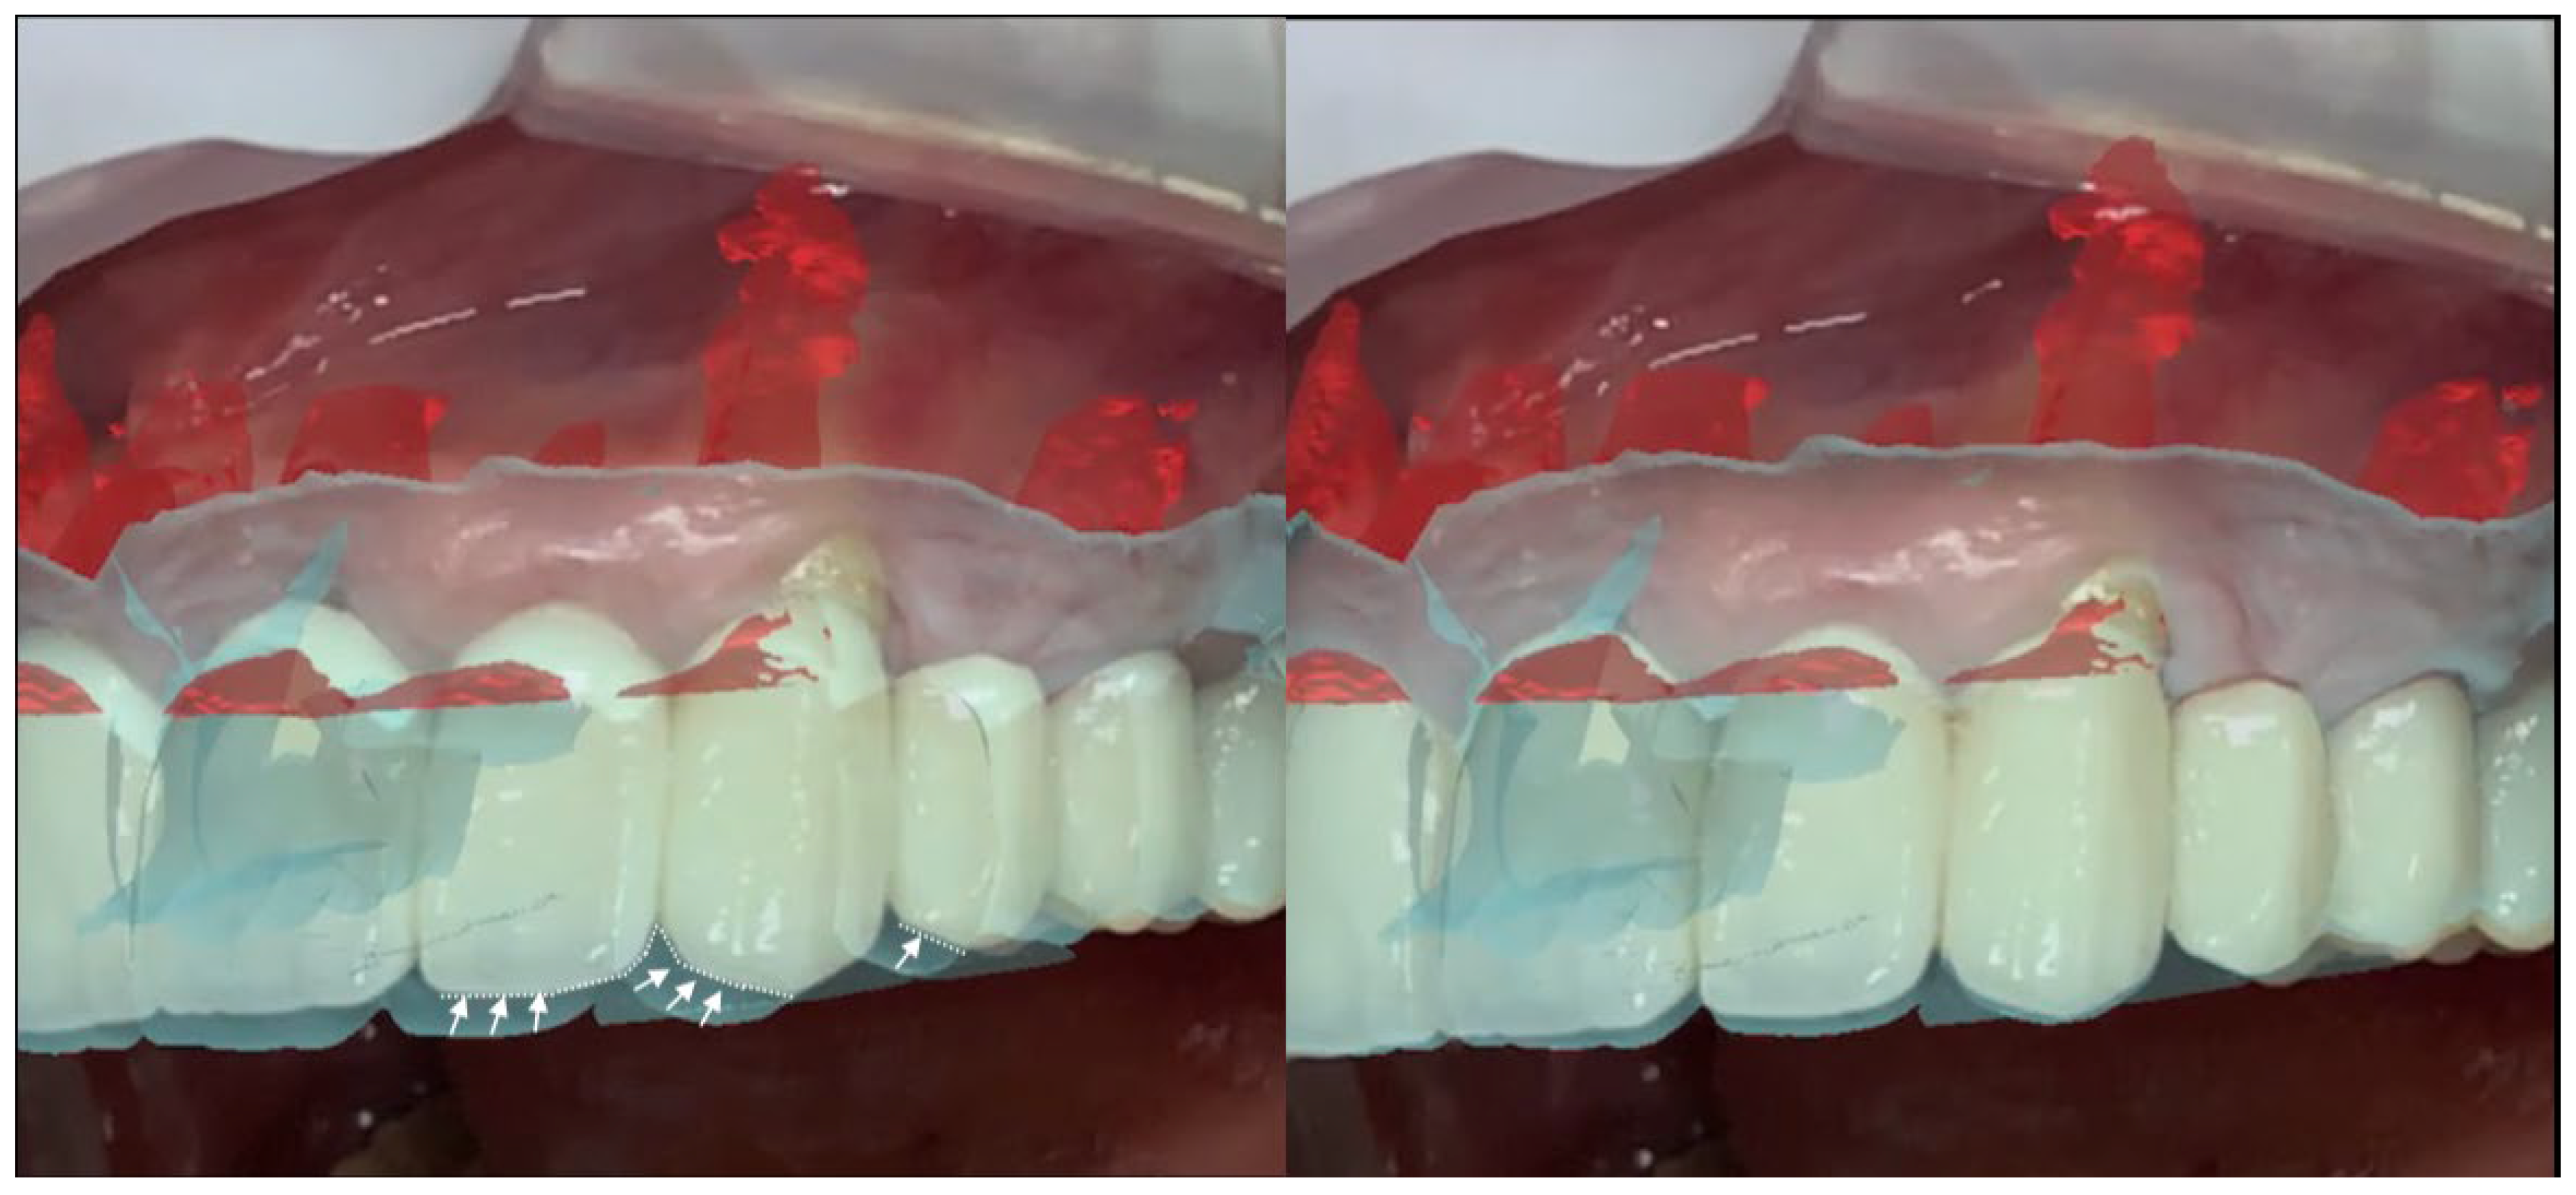

All patients were treated under local anesthesia using (4% Articaine with Adrenaline 1:100,000 or 1:50,000 for better bleeding control). The iPad device was positioned in front of the surgical field, and the operator visualized the overlapped digital apex and root canal. The correct overlap was checked in the six degrees of freedom by rotating the device around the clinical scene in different projections (Figure 3 and Figure 4). A semilunar flap was elevated to expose the surgical site most proximal to the root’s apex according to the AR guide. The alveolar bone was carefully removed using a low-speed round bur under copious irrigation, guided by the superimposed 3D models. The root was resected at least 3 mm coronal to the apex to cut the apical portion of the root, with a buccal bevel, to grant clinical view and access. After the resection of the root, a blu methylene with a micro-brush was inserted into the surgery zone and over the cut root to highlight the contour of the root, the main and accessory canal for the retrograde preparation. In the meanwhile, minimal bone removal as well as a lack of trauma to the neighbour roots and apexes was ensured (Figure 5). The infra bony lesion was removed carefully, and the residual root was cleaned through courettes and an ultrasonic scaler. The retrograde preparation was carried out with ultrasonic diamond tips and a bioceramic root-end filling material was placed. The flap was sutured with 6–0 sutures, and a postoperative periapical rx was taken to confirm the resection margin and retrograde filling material location.

Figure 5. Third case, apicectomy of the 1.1.